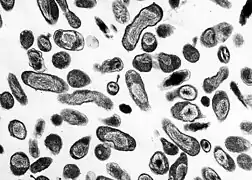

| Immunohistochemical detection of C. burnetii in resected cardiac valve of a 60-year-old man with Q fever endocarditis, Cayenne, French Guiana: Monoclonal antibodies against C. burnetii and hematoxylin were used for staining; original magnification is ×50. | |